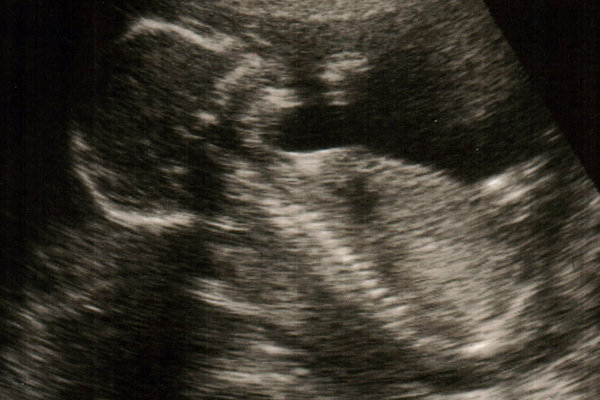

18 hetes ultrahangunk! [/img]